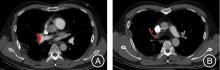

Objective This research aimed to study the values of the deep learning convolutional neural network model trained from scratch(DL?CNN(fs)) in assessment of acute pulmonary thromboembolism (APE). Methods A total of 214 patients with suspected APE who underwent computed tomography pulmonary angiography(CTPA) were retrospectively studied, including 137 patients with APE and 77 patients without APE. The presence or absence of APE was determined by the radiologists based on CTPA. The Qanadli score, Mastora score and other parameters on CTPA were measured by the radiologists. The clot volumes and distribution were measured by U?net model which was based on DL?CNN. The performance of DL?CNN(fs) in measuring clot distribution and clot burden was evaluated. The correlation between clot burden and Qanadli score, Mastora score and other CTPA parameters was calculated. Results Sensitivity, specificity and AUC of the central pulmonary artery clot distribution measured by DL?CNN(fs) were 100%, 16.8%, AUC = 0.584 (95%CI: 0.508 ~ 0.661). Sensitivity, specificity and AUC of the peripheral pulmonary artery clot distribution were high (R1?R9, 60.8% ~ 95.2%,67.9% ~ 87.1%,0.740 ~ 0.844; L1?L10, 64.6% ~ 93.4%, 62.7% ~ 83.1%, 0.732 ~ 0.791). Strong positive correlation was noted between clot volumes measured by DL?CNN (fs) model and Qanadli score (r = 0.867,P < 0.001), as well as Mastora score (r = 0.854, P < 0.001). Clot volumes measured by DL?CNN (fs) model were correlated with the right ventricular functional parameters(right ventricular diameter/left ventricular diameter, right ventricular area/left ventricular area,r = 0.549, 0.559, P < 0.01). Conclusion The DL?CNN (fs) model has high value in detecting peripheral pulmonary embolism, and its diagnostic specificity for central pulmonary embolism needs to be further improved. The clot volumes from DL?CNN(fs) were correlated with metrics of pulmonary embolism and right ventricular function, which may help doctors to quickly evaluate the clot burden and risk stratification of acute pulmonary thromboembolism.